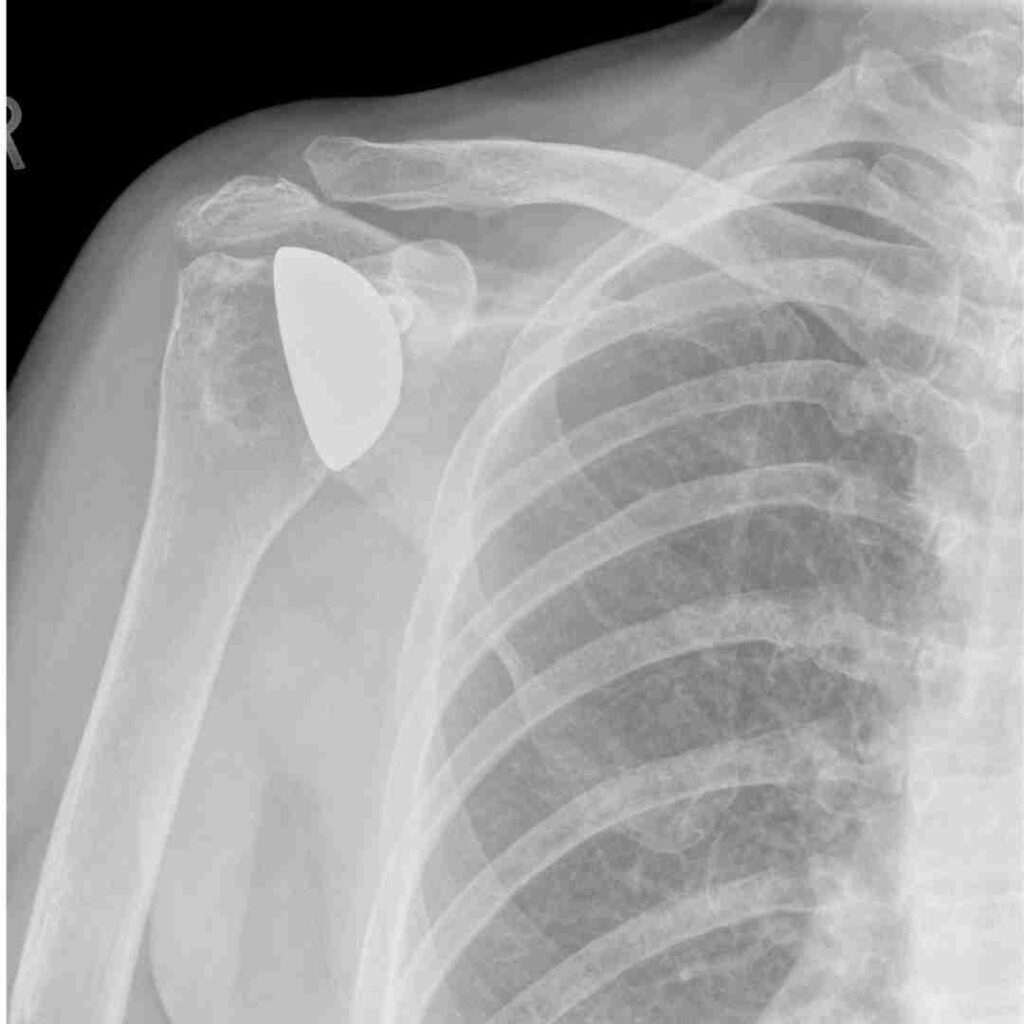

AC Joint Fixation Surgery is a specialized procedure used to treat severe acromioclavicular (AC) joint dislocation or separation. The AC joint, where the clavicle (collarbone) meets the acromion of the shoulder blade, can be injured during falls, sports accidents, or trauma. When the ligaments stabilizing this joint are torn or stretched, surgical intervention is needed to realign and fix the joint—this is where AC joint fixation surgery plays a vital role.

AC Joint Fixation Surgery in Hyderabad focuses on diagnosing and treating injuries of the acromioclavicular (AC) joint, which connects the collarbone to the shoulder. This condition commonly causes shoulder pain, swelling, weakness, and difficulty lifting the arm. The main goal of surgery is to restore joint stability, reduce pain, and bring back normal shoulder movement so patients can return to daily activities safely.AC joint injuries often occur due to falls, road traffic accidents, sports injuries, or heavy impact to the shoulder. In some cases, ligaments around the joint are torn, making surgery necessary for proper healing. In Hyderabad, treatment plans are personalized based on the type of injury, severity, patient age, activity level, and overall health. Advanced surgical techniques help ensure strong fixation, faster recovery, and long-term shoulder function.

Diagnosis of AC Joint Problems

X-ray or MRI scan